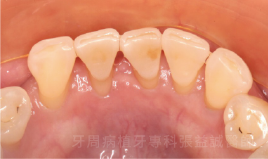

牙周病水雷射治療案例分享

治療前 治療後

治療前

治療後